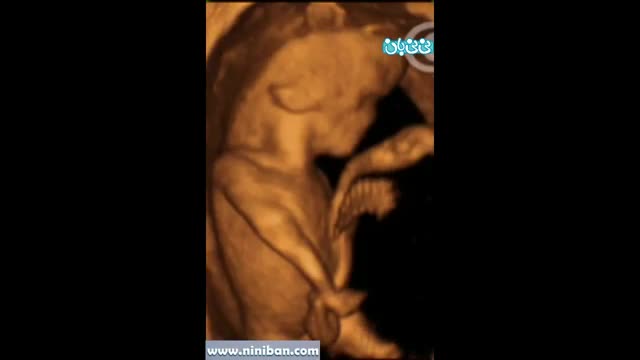

سونوگرافی چهار بعدی در بارداری هفته یازدهم - 1